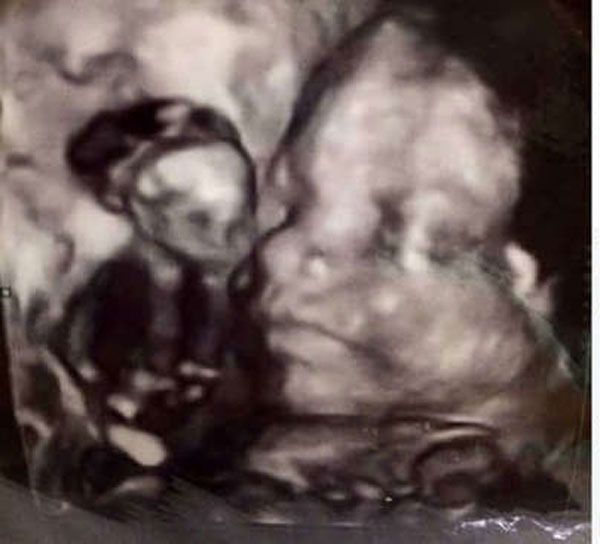

ಫಗಾನ್ ಎಂಬ ತಾಯಿಯ ಹೊಟ್ಟೆಯೊಳಗಿದ್ದ ಈ ಮಗುವು ಏನೇ ಮಾಡಿದರು ಅಲ್ಟ್ರಾಸೌಂಡ್ ಸ್ಕ್ಯಾನ್ ಅಲ್ಲಿ ತನ್ನ ಮುಖವನ್ನ ತೋರಿಸುತ್ತಿರಲಿಲ್ಲ. ಆಗ, ಫಗಾನ್ನ ದೊಡ್ಡ ಮಗಳಾದ ಮೋಲ್ಲಿ ತನ್ನ ಅಮ್ಮನ ಹೊಟ್ಟೆಯ ಹತ್ತಿರ ಬಂದು ಪಿಸುಗುಡಲು ಶುರು ಮಾಡಿದಳು. ಆಗ ಹೊಟ್ಟೆಯಲ್ಲಿದ್ದ ಮಗುವಿಗೆ ಏನಾಯಿತೋ ಗೊತ್ತಿಲ್ಲ, ಅದರ ಮುಖ ಅರಳಿಕೊಂಡು, ಒಂದು ದೊಡ್ಡ ನಗೆಯನ್ನ ಬೀರಿತು. ಹೀಗಾಗಿಯೇ ಈ ಮಗುವಿಗೆ “ಬ್ರಿಟನ್ನ್ನಿನ ಅತ್ಯಂತ ಆನಂದಮಯ ಮಗು” ಎಂಬ ಖ್ಯಾತಿ ಬಂದಿತು.